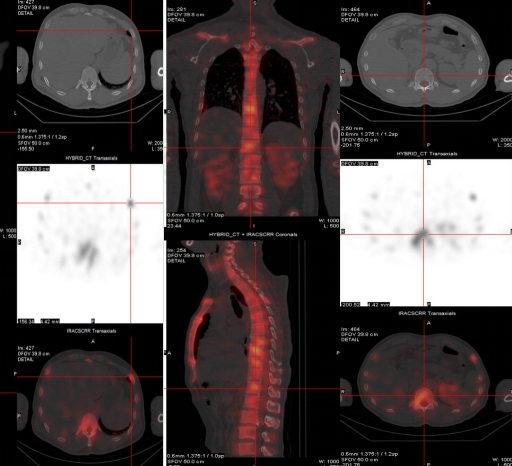

(病例三)患者,男 44岁,左肺下叶恶性肿瘤(T4N2M1c,IVB),纵膈继发性恶性肿瘤,胸膜继发性恶性肿瘤,骨和骨髓继发性恶性肿瘤。靶向药物治疗后为评估骨继发恶性肿瘤来诊。MIP图示:与2021-8-3日片比,2021-12-21日片示左侧第8后肋病灶放射性摄取明显减低,左侧第3后肋、胸骨柄片状放射性摄取范围减小,右侧第6前肋、L2椎体放射性摄取范围无明显变化。结论:与2021-8-3日片比:左侧第8后肋、左侧第3后肋、胸骨柄病灶骨盐代谢明显减低,提示肿瘤细胞活性减低;右侧第6前肋、L2椎体病灶骨盐代谢无明显变化。